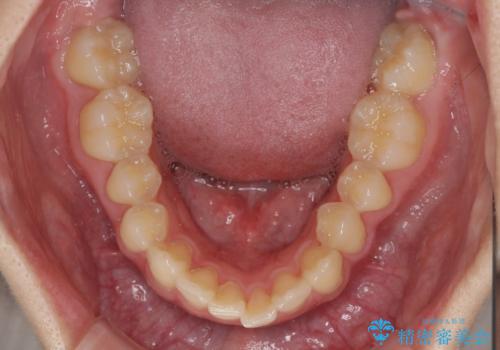

- 咬み合わせが悪いとのことで来院された患者様です。

思っていたよりも早くクロスバイトは改善され、歯髄壊死に至ることなく、無事に治療を終えることができました。